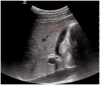

Right upper quadrant and epigastric abdominal pain are common presenting complaints in the emergency department. With increasing access to point-of-care ultrasound, emergency physicians now have an added tool to help identify biliary problems as a cause of a patient's right upper quadrant pain. Point-of-care ultrasound has a sensitivity of 89.8% (95% CI 86.4-92.5%) and specificity of 88.0% (83.7-91.4%) for cholelithiasis, very similar to radiology-performed ultrasonography. In addition to assessment for cholelithiasis and cholecystitis, point-of-care ultrasound can help emergency physicians to determine whether the biliary system is the source of infection in patients with suspected sepsis. Use of point-of-care ultrasound for the assessment of the biliary system has resulted in more rapid diagnosis, decreasing costs, and shorter emergency department length of stay.